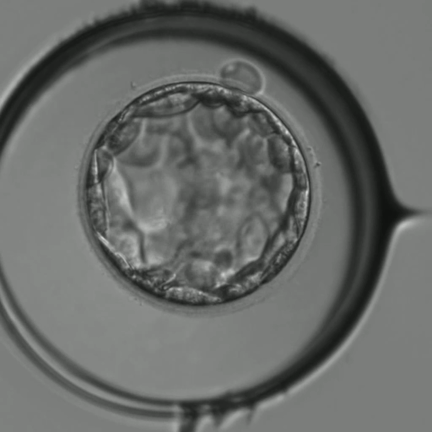

• 胚盤胞の収縮と拡張は成長のために必要ですの記事動画